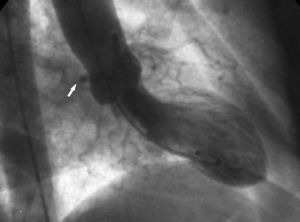

International groups are calling for registries including at least those anomalies that cause the majority of the clinical events (sudden death and myocardial ischemia) attributed to CAA,5-7 constituted by those originating in the contralateral or "wrong" sinus of Valsalva. This group includes single vessel coronary arteries ("hyperdominance" in the classification of Rigatelli et al4), since they have to supply blood to the myocardium arising from a single coronary ostium and establish routes that occasionally are similar to those of the CAA with origin in the wrong sinus of Valsalva (Figure 1).

Figure 1. Coronary arteriografía in left anterior oblique projection showing a single vessel right coronary artery.

2. The "aortic root" sign. In ventriculography, the right anterior oblique projection shows the contour of the anomalous Cx and follows its course as it passes behind right coronary sinus (Figure 10).

Figure 10. Ventriculography in right anterior oblique projection showing the contour of the anomalous circumflex artery (arrow) passing behind right coronary sinus; this is known as the aortic root sign or Page's sign.